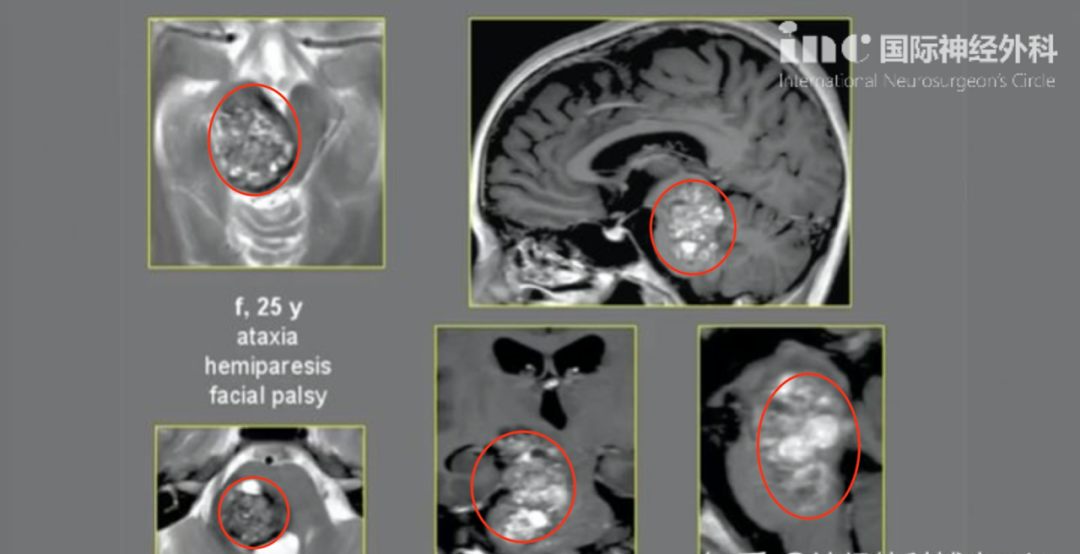

这个盘踞在脑干核心区(中脑-脑桥)的巨大海绵状血管瘤,影像呈现如同被虫蛀空的树干般布满骇人的病变斑点,每一次出血都可能造成可怕的神经损伤。

INC巴特朗菲教授曾做关于脑干海绵状血管瘤的专题报告,其中介绍了这则巨大脑干海绵状血管瘤的全切案例,本来已经偏瘫、面瘫的25岁女性经历了一场安全且全切的手术切除,从此之后站了起来。

基本情况:

25岁青年女性,偏瘫、面瘫,共济失调

诊断:

(中脑-脑桥)脑干巨大海绵状血管瘤。术前影像:中脑、脑桥巨大占位

手术结果:

脑干海绵状血管瘤全切,手术顺利

术后恢复:

无新发神经功能损伤,术前症状明显改善,肢体瘫痪、面瘫好转,能自行行走,治疗效果满意。术后5年随访,无复发,我们可以看到图片中的女孩已经站了起来。